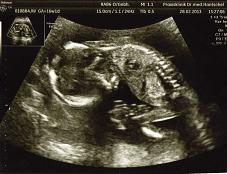

es wird zu 80 % ein junge! er hat die ganze zeit die hand davor gehabt und dann hat er sich doch gezeigt! SS 10 cm und 150 g leicht. hier ist er, unser süßer...

Bild zu Outing! :-D - Forum für August - Mamis

dankeschön! naja schüchtern eher ni. ich denke mal er hat sich schon am schnippi gespielt. ja, da war einer. haben alles gesehen. aber der doc lachte und sagte vorsichtshalber zu 80%. aber man hat´s zu 100% gesehen. echt niedlich.